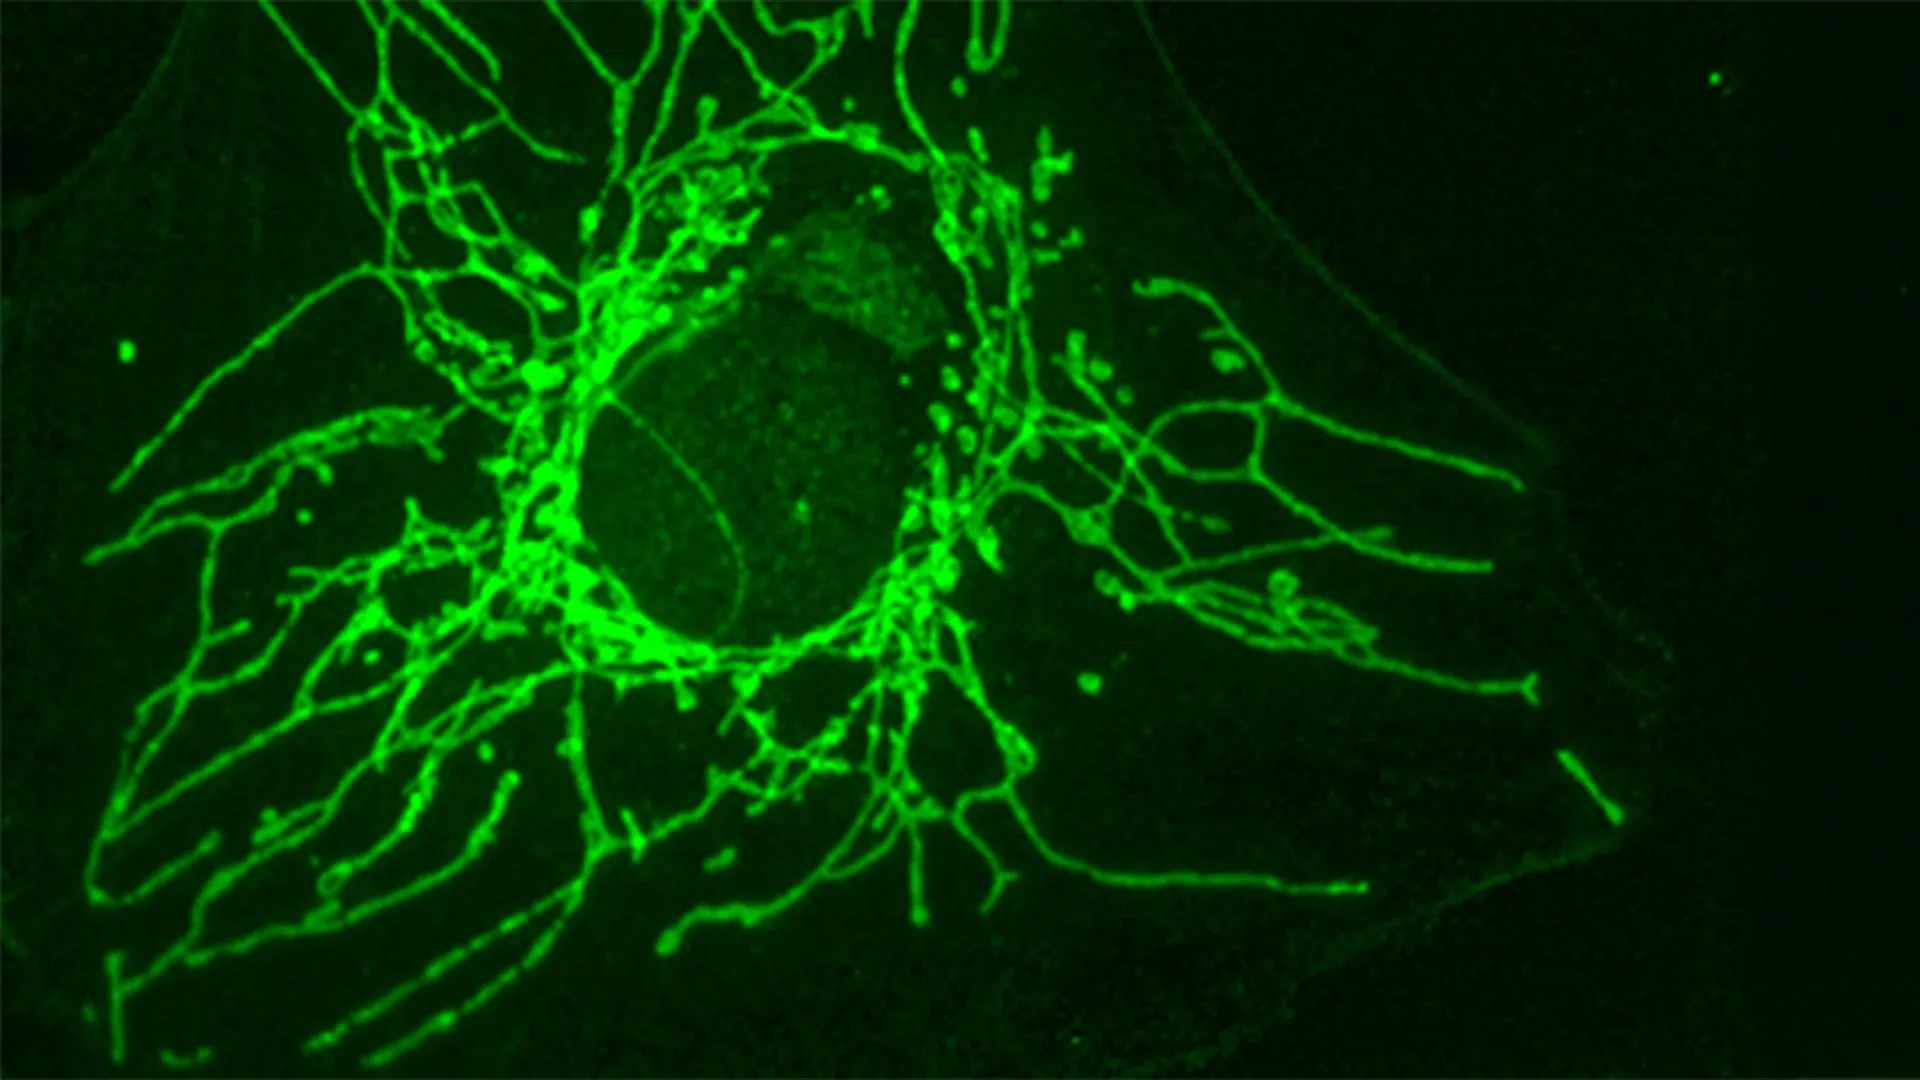

The pivotal revelation emerged when scientists observed that the D-version of cysteine, referred to as D-Cys, exhibited a profound capacity to inhibit the growth of certain cancer cell lines in in vitro experiments. Crucially, this inhibitory effect was highly selective; healthy cells remained largely unaffected by the presence of D-Cys. This differential response between cancerous and non-cancerous cells immediately signaled a potential for targeted therapy. Dr. Joséphine Zangari, a PhD student in Professor Martinou’s laboratory and the study’s lead author, elucidated the underlying mechanism for this selectivity: "This divergence between malignant and healthy cells is readily explained: D-Cys gains entry into cells through a specialized transporter protein that is predominantly expressed on the surface of particular cancer cells." She further elaborated, "Indeed, we observed that if we induced healthy cells to express this same transporter on their surface, those cells subsequently ceased proliferating when exposed to D-Cys." This critical insight pinpoints a specific vulnerability in certain cancer cells that can be exploited for therapeutic gain.

To unravel the precise molecular mechanisms by which D-Cys exerts its detrimental effects on cancer cells, the researchers collaborated with Professor Roland Lill and his team at the University of Marburg. Their joint efforts uncovered that D-Cys directly interferes with an indispensable enzyme named NFS1. This enzyme resides within the mitochondria, often dubbed the "powerhouses" of the cell due to their central role in energy production. NFS1 is vital for the synthesis of iron-sulfur clusters, intricate small structures that are absolutely essential cofactors for a multitude of fundamental cellular processes. These processes include cellular respiration, the intricate biochemical pathways that generate ATP (the cell’s primary energy currency); the production of DNA and RNA, which are the blueprints and messengers of genetic information; and the maintenance of genomic integrity, ensuring accurate replication and repair of the cell’s genetic material.

When D-Cys blocks the activity of NFS1, the cascading consequences for cancer cells are severe and multifaceted. The disruption of iron-sulfur cluster production leads to a significant reduction in cellular respiration, effectively starving the cells of the energy they require for rapid growth. Concurrently, the impaired synthesis and repair of DNA result in an accumulation of genetic damage, triggering cellular checkpoints that halt the cell cycle. Unable to repair the damage or meet their metabolic demands, the affected cancer cells are prevented from continuing to grow and divide, effectively arresting their proliferative capacity. This multi-pronged attack on fundamental cellular functions makes D-Cys a potent metabolic disruptor for susceptible cancer cells.